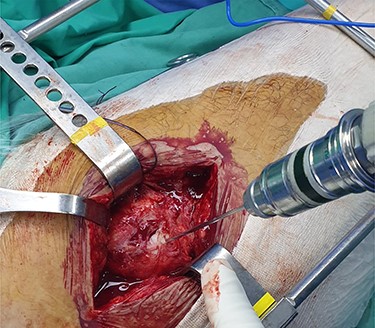

The patient is placed in lateral decubitus position. There is no need of a traction table and fluoroscopy in order to identify the intramedullary canal and the nail inserted. Palpating the prominence of the greater trochanter on the lateral side, an incision is made over it and can be extended distally and proximally. The fasciae latae is carefully incised. The femoral diaphysis and the origin of vastus lateralis are identified. Above the origin of vastus lateralis, k-wires are drilled in order to identify, the anterior and posterior margins of the intramedullary nail in the sagittal plane and mark them and can be left in place (Figs 1 and 2). This is easily performed due to the metal-on-metal effect that is produced during drilling (Fig. 3). Knowing the anterior (point A) and posterior (point P) margins of the intramedullary nail, multiple drillings are performed proximally and perpendicular to the median of the (AP) side of the formed triangle (TAP). The drilling point where no metal-on-metal effect is produced corresponds to the proximal endpoint of the intramedullary nail (point T). Those points form a triangle (TAP) on the lateral side of the femur with the top (T) highlighting the endpoint of the intramedullary nail, and the sides the anterior (A) and posterior (P) margins (Fig. 4). Drilling with k-wires also helps us determine the depth of the nail.

Image showing the metal on metal effect that is produced when the k-wire has reached the outer surface of the nail in different planes.